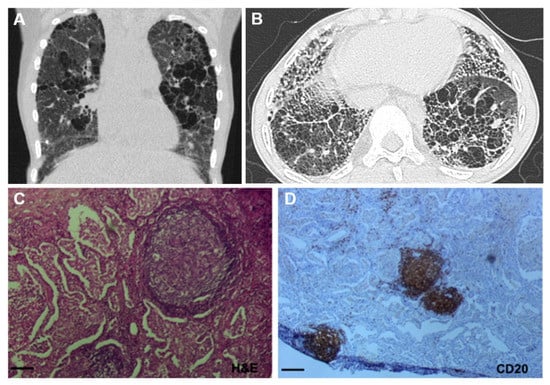

| Radiological Findings |

| Ground glass opacities |

| Septal thickening |

| Honeycombing |

| Crazy paving |

| Cysts |

| Histopathological Findings |

| Fibrosis |

| Lymphoid follicles with germinal left organization |

| Inflammatory infiltrate |

| Alveolar hemorrhage |